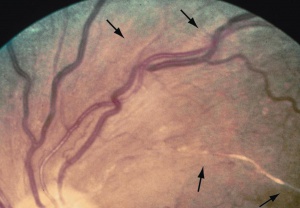

Stadio 1: restringimento, aumento del riflesso parietale e tortuosità dei vasi retinici;

Stadio 2: al restringimento ed alla tortuosità si associano gli schiacciamenti artero-venosi ( schiacciamenti A-V ) che a loro volta possono essere suddivisi in 4 gradi di gravità;